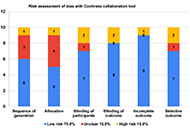

This article belongs to the special issue Emerging Infectious Diseases Innovative technologies for identifying oral potentially malignant disorders: a systematic reviewOpen AccessSystematic ReviewThe cardiovascular system remains vulnerable to a multitude of threats, including infections, inflammation, and oxidative stress. These factors contribute significantly to the development and progre [...] Read more.Supraja Salwaji ... Giuseppe MinerviniPublished: May 05, 2025 Explor Med. 2025;6:1001315

Innovative technologies for identifying oral potentially malignant disorders: a systematic reviewOpen AccessSystematic ReviewThe cardiovascular system remains vulnerable to a multitude of threats, including infections, inflammation, and oxidative stress. These factors contribute significantly to the development and progre [...] Read more.Supraja Salwaji ... Giuseppe MinerviniPublished: May 05, 2025 Explor Med. 2025;6:1001315